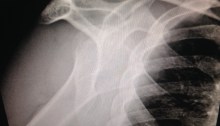

Dislocated Shoulder

Hello again to all our readers! (if any :P) I hope you all of you are enjoying your Ramadan as much as we do. However, this Ramadan is slightly different for us, a challenging one in fact. On the 3rd day of Ramadan CheeseBoy slipped and fell, and had his shoulder dislocated. The emergency doctors at the…